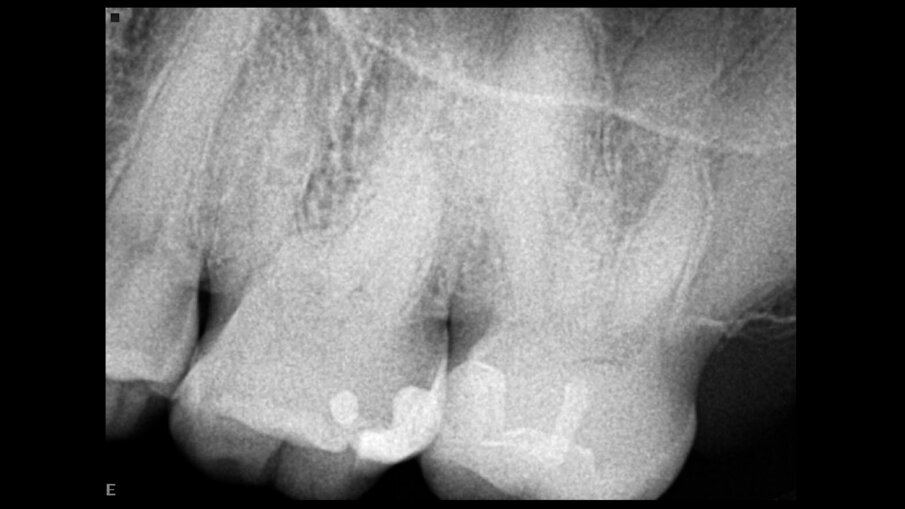

Obturacija je završena, a neposredni postoperativni rendgenski snimci su pokazali da su svi kanali popunjeni i zapečaćeni (Sl. 7a–c).

Sl.7a-c: Rendgenski snimci neposredno posle operacije koji pokazuju 3D punjenje sistema kanala korena pod različitim uglovima